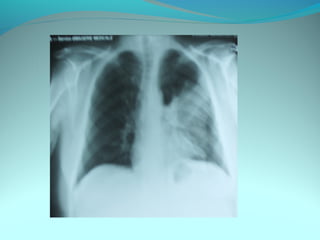

Opacité occupant la partie externe du 1/3 infer du poumon droit

dense et homogene ovalaire de 8cm de grand axe vertical

La limite externe se confend avec une opacité d’environ 1cm comble

les coupole costodiaphragmatique droit

Limitée a sa partie sup par la petit sessure qui est epaisse et pas de

lyse costale

 DIAGNOSTIC :DIAGNOSTIC :

 1_1_cancer bronchique droit( d epaississement)

 2_2_ kyste hydatique au stade sain